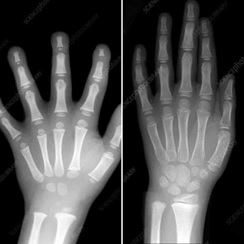

Do not be in a rush for this Covid ‘catch up’ that is appearing – this is a fallacy. Look at the image below. The X-ray on the left is a 4 year old child’s hand bone structure and the one on the right belongs to an 8 year old. To start popping a pencil in their hands, to ‘catch up’, is (as you can tell) not going to make much difference to their ability to write better when older. Be patient and know your child is constantly developing and ever changing.